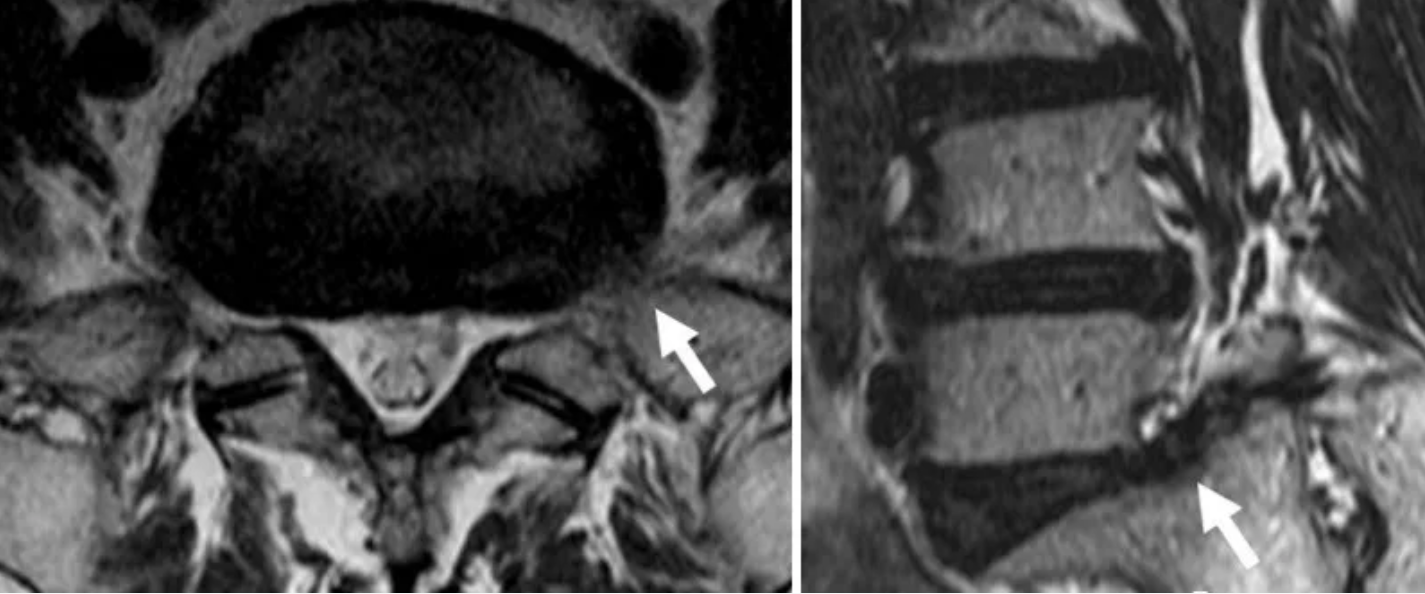

注意:腰椎MR平扫常导致本病漏诊,一旦发现腰椎骶化或骶椎腰化,而患者又比较年轻,应加扫冠状位压脂序列,或是配合 CT薄层扫描进行联合诊断。

由于Bertolotti综合征常合并上位椎间盘突出、退变以及上位椎体不稳,上述脊柱退行性改变也会导致腰疼,因此很容易导致本病的漏诊。例如某腰疼患者行脊柱MR平扫发现腰4/5椎间盘突出,随即临床对腰4/5椎间隙进行彻底的减压治疗,而术后患者的腰疼症状却无明显改善,这往往就是漏诊Bertolotti综合征所致。因此,对于青壮年腰痛或伴下肢放射痛,特别是发生在L4/5水平的,术前应排除Bertolotti综合征,以免引起医疗纠纷。